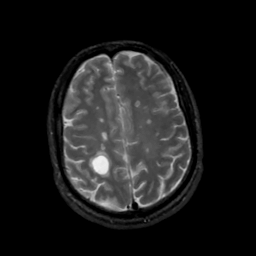

MR Study #5, March 10, 1991 -- Slice #38